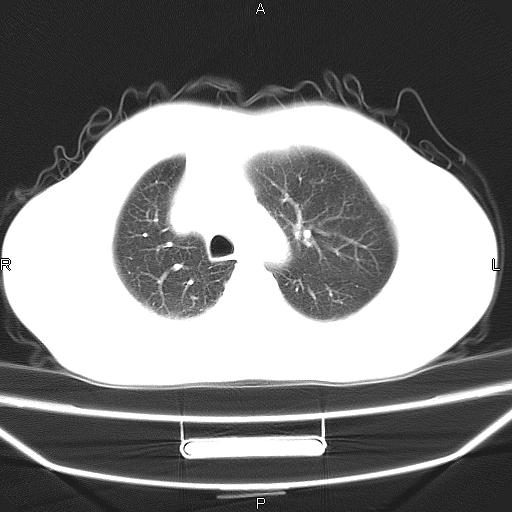

患者,男。50岁。近几日有咳嗽症状,无其他不适,既往病史无,考虑膈疝。请前辈们看看指导指导。

膈膨升,左下肺通气不良,膈肌好像还完整。

符合隔膨升,膈肌较完整。